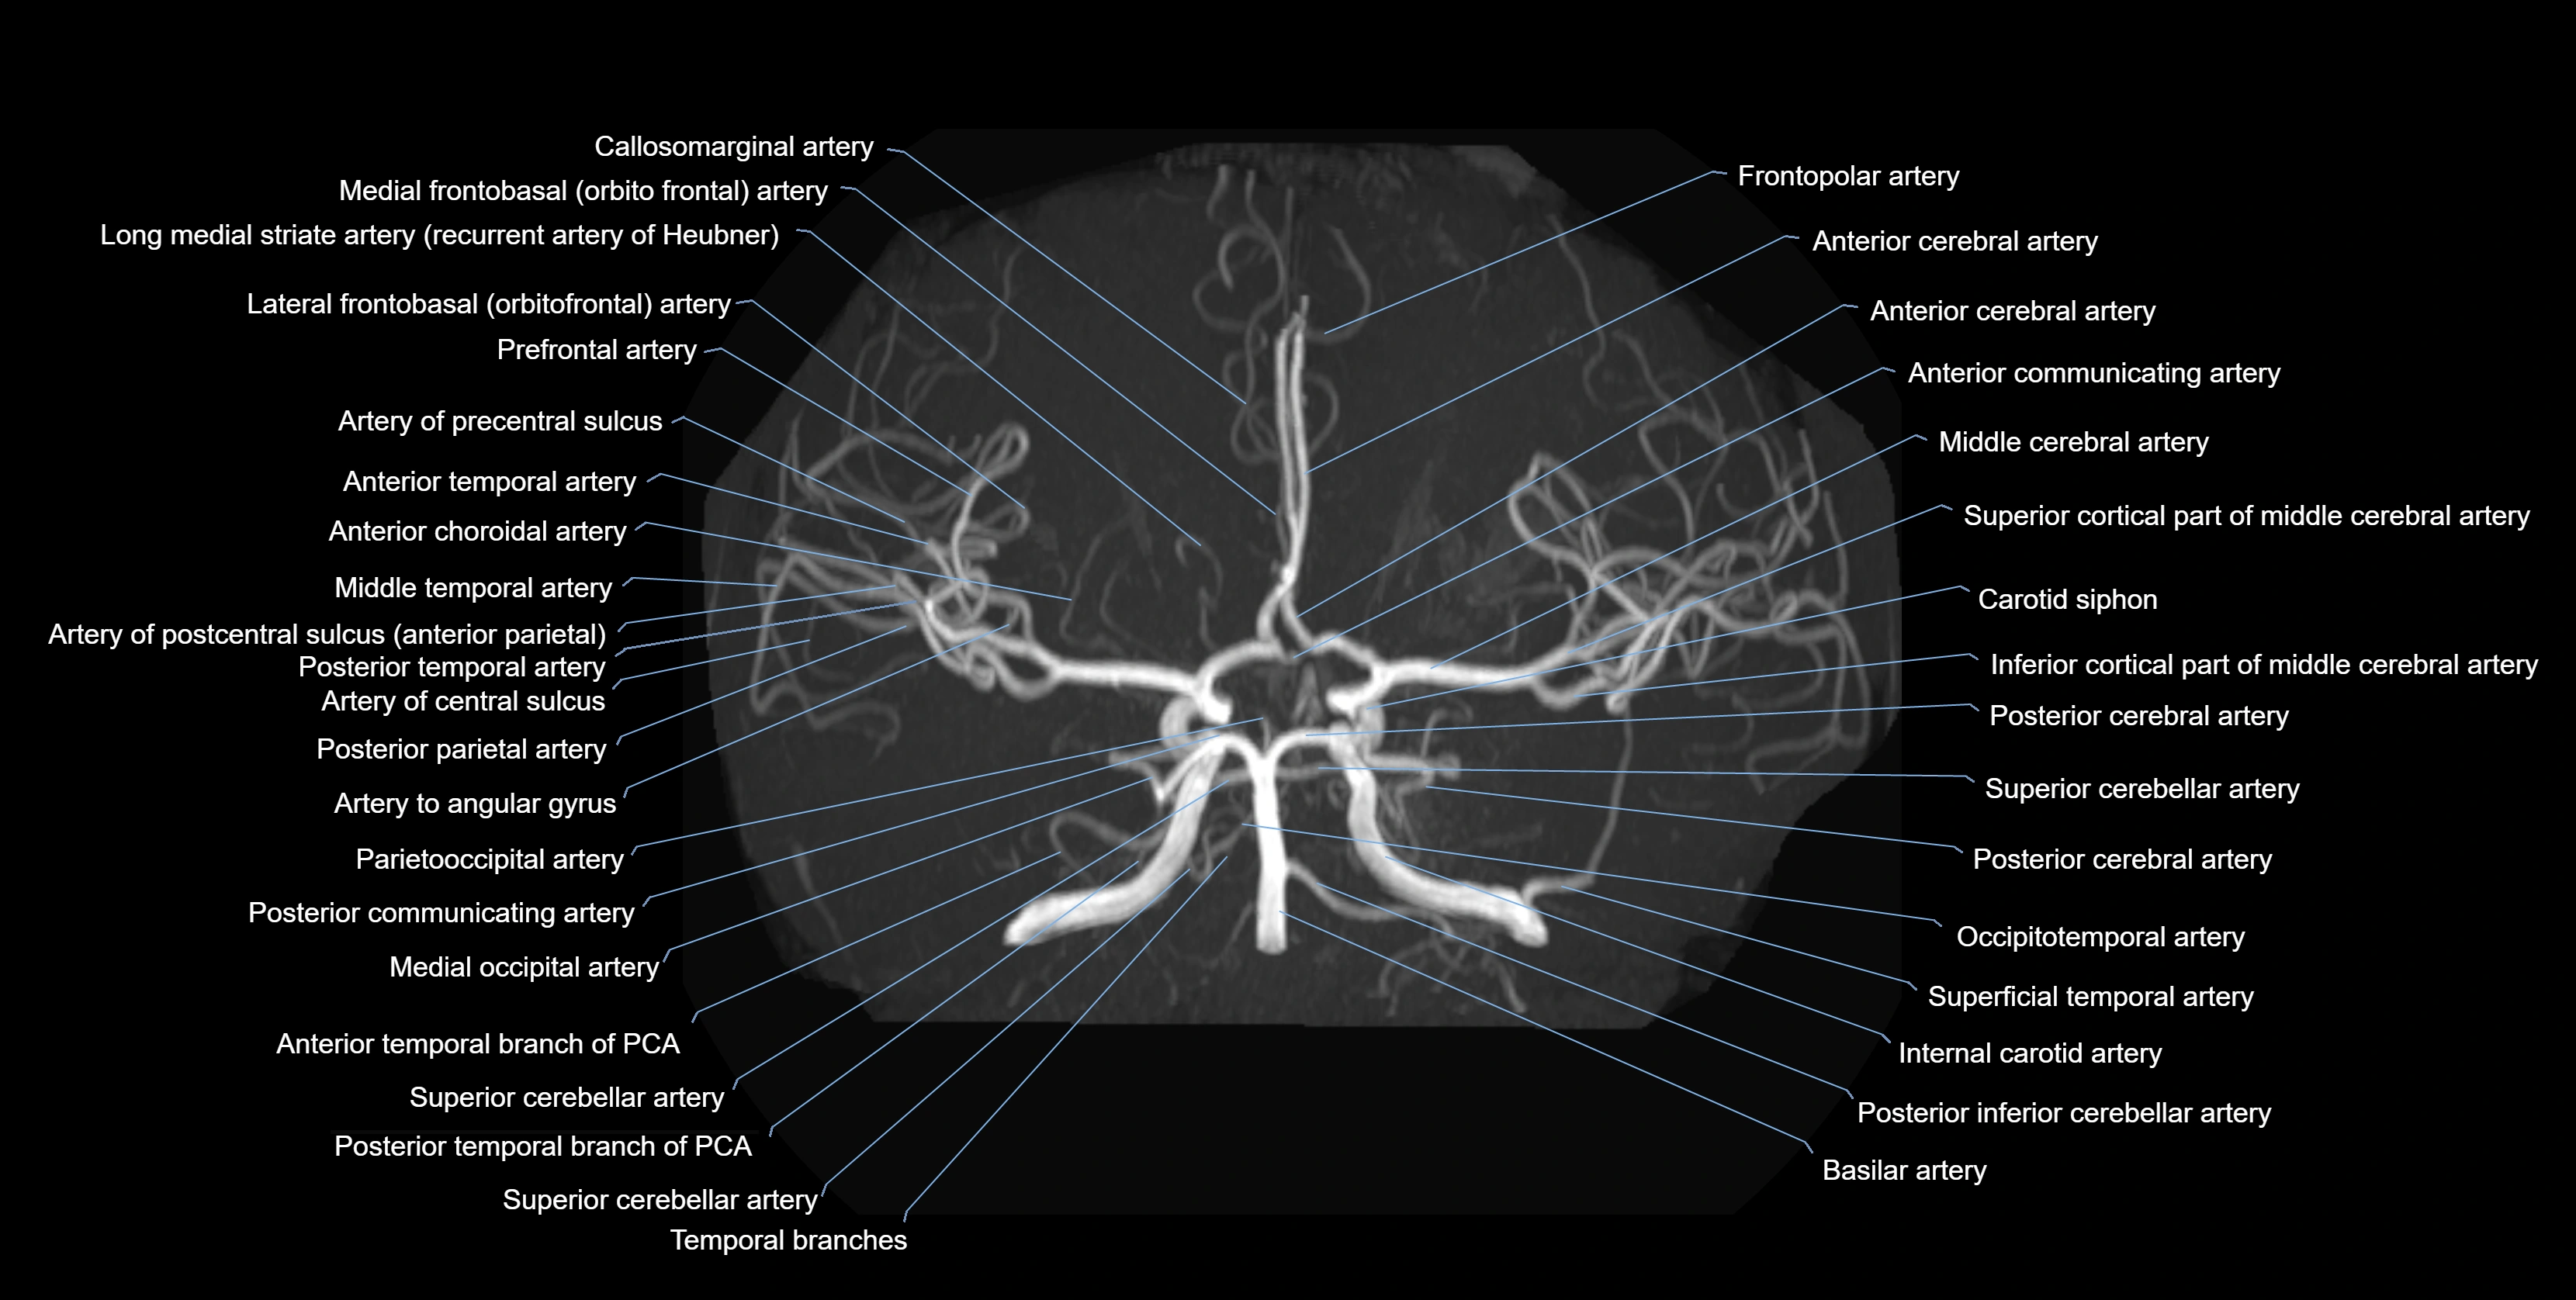

CTA (CT Angiography):

• Opacified with iodinated contrast, AChA appears as a bright high-attenuation vessel

• Visualized from ICA origin along optic tract toward choroid plexus

• 3D reconstructions depict its course and relation to adjacent arteries

• Gold standard for identifying aneurysms, occlusion, or vascular anomalies